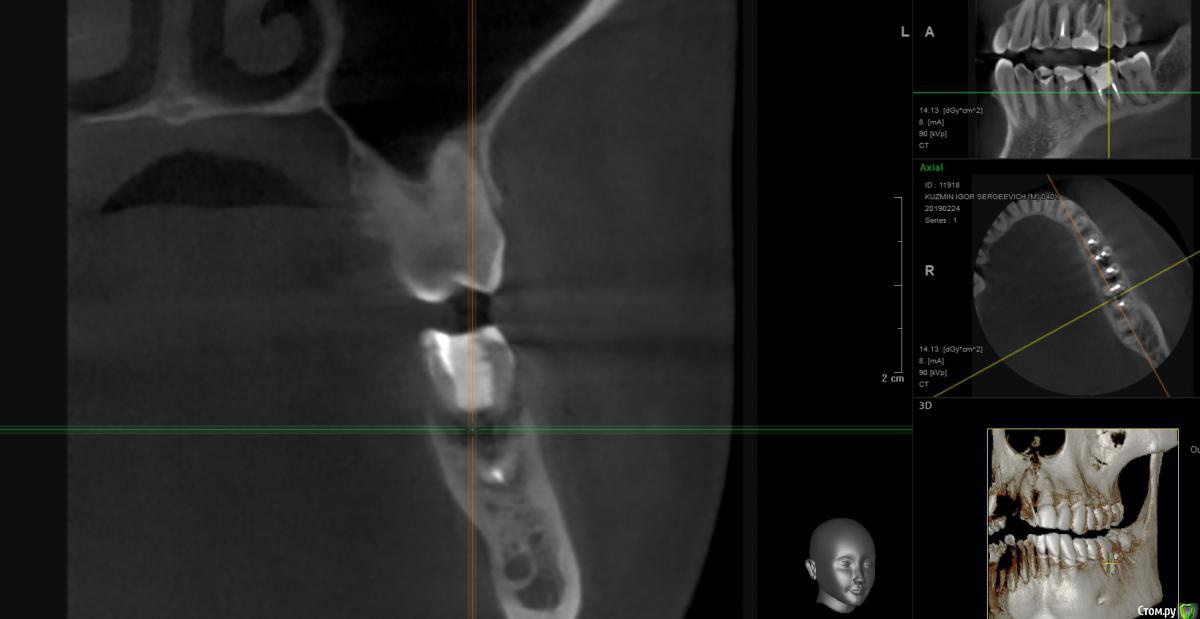

isk0 Опубликовано 10 марта, 2019 Поделиться Опубликовано 10 марта, 2019 Так случилось, что с пол года назад на десне 6 зуба образовался свищ. Обратился к врачам порекомендовал кто-то удалить 6 зуб. По глупости своей решил попробовать сделать лоскутную операцию на этот зуб. Все почистили, помыли, но зуб снова воспалился через две недели.В это время я перелечивал каналы соседнего 7-го зуба и 5-го зуба. По прошествии 5 месяцев закончив лечить другие зубы, я сделал контрольное кт и когда я сравнил оба кт с разницей 5 мес. я увидел следующее Мало того, что под 6 зубом убыль кости спрогрессировала, так еще не понятно, что произошло с 7 зубом...В общем я снова по врачам,Один врач сказал удалить 6 и 7 зуб и через два месяца ставить туда имплантаты. Ок подумал я, но меня смутило, врач меня заверил костной пластики на 6 зуб не нужно будет поставит так..., по 7 зубу вопросов нет.Второй врач сказал удалить 6 зуб, заложить костный материал на его место и накрыть мембраной, заодно почистив область бифуркации 7 зуба. И ждать 3-4 месяца результата. В том числе он меня уверил что убыль кости в фуркации 7-го зуба связана с 6-м зубом (это и так понятно). И если убрать 6 зуб, разрежение фуркации 7-ки остановится и что воспалительного процесса там нет и тем более кисты.срез кт по 7-му зубу И вот уважаемые доктора я на перепутье. Однозначно только одно понимаю, что 6-ку удалять. Но как быть с 7 зубом и нужна ли все таки костная пластика на 6-ку послу удаления.... Короткий имплант не поставишь все таки зуб большую нагрузку несет жевательную, под углом мастерить тоже что-то не хочется, а ставить полноценной длины 10 мм и более , слишком близко канал нижнечелюстного нерва идет , не хочется вечную анестезию получить. Заранее спасибо. Ссылка на комментарий

Борис80 Опубликовано 12 марта, 2019 Поделиться Опубликовано 12 марта, 2019 Неудобные срезы, короткий имплант это 6 мм , у вас там больше, имплант 8-8.5 мм и более это уже отличной длины, достаточной для жевательного зубав области верхушек 7 есть воспаление, но данных недостаточно, чтобы сказать однозначно Ссылка на комментарий

Дмитрий Л. Опубликовано 12 марта, 2019 Поделиться Опубликовано 12 марта, 2019 Ничего там не спрогрессировало. Лечите пародонтит. 1 Ссылка на комментарий